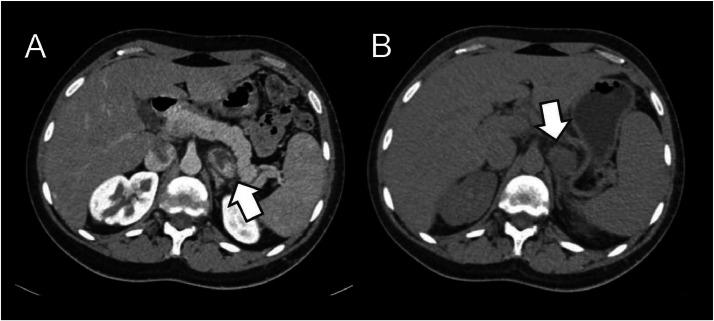

We present the case of a 22-year-old male with a left adrenal pheochromocytoma, initially diagnosed during a workup for thoracic pain. The patient's tumor was refractory to medical management, and surgical resection was ruled out due to high cardiovascular risk, stemming from cyanotic congenital heart disease, aortic aneurysm, and factor VII deficiency. The patient underwent adrenal artery embolization (AAE) as a salvage treatment. Following the procedure, there was an initial reduction in hypertensive crises and biochemical markers, with plasma normetanephrine levels decreasing from 1490 pg/mL to 313 pg/mL. However, over subsequent months, the patient experienced symptom recurrence, and biochemical relapse occurred, with normetanephrine levels rising to 742 pg/mL by 3 months postprocedure. This case highlights the potential for AAE to provide short-term symptom relief and biochemical response; nevertheless, it may not be an effective long-term curative option. More collaborative and prospective studies are needed to assess its success and efficacy.

我们报告一例22岁男性左肾上腺嗜铬细胞瘤病例,最初在因胸痛进行检查时被诊断出来。患者的肿瘤对药物治疗无效,由于存在紫绀型先天性心脏病、主动脉瘤和凝血因子VII缺乏导致的高心血管风险,手术切除被排除。患者接受了肾上腺动脉栓塞术(AAE)作为挽救治疗。术后,高血压危象和生化指标最初有所下降,血浆去甲肾上腺素水平从1490 pg/mL降至313 pg/mL。然而,在随后的几个月里,患者症状复发,生化指标复发,术后3个月时去甲肾上腺素水平升至742 pg/mL。该病例凸显了AAE提供短期症状缓解和生化反应的潜力;然而,它可能不是一种有效的长期治愈选择。需要更多的合作性前瞻性研究来评估其成功率和疗效。